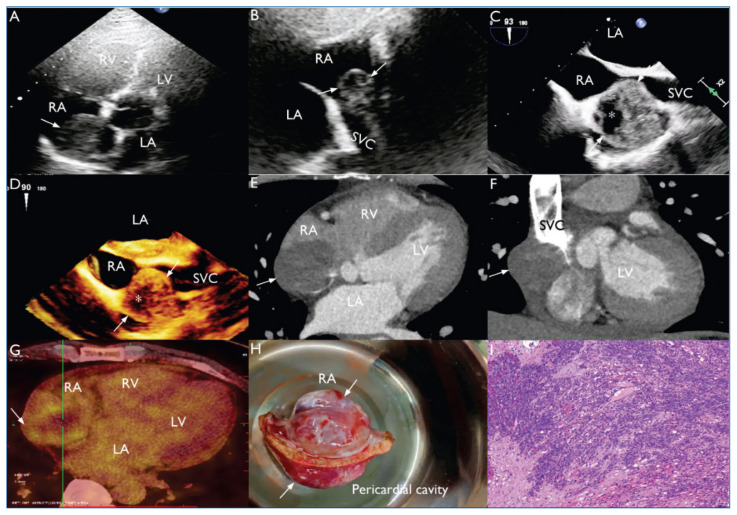

Primary cardiac angiosarcoma: an extremely rare entity presenting with palpitations.

原发性心脏血管肉瘤:一种以心悸为表现的极为罕见的疾病。